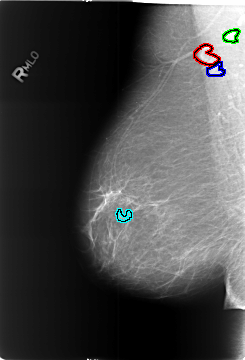

B_3451_1.RIGHT_MLO

RIGHT_MLO LINES 5760 PIXELS_PER_LINE 3912 BITS_PER_PIXEL 12 RESOLUTION 50 OVERLAY

FILE: B_3451_1.RIGHT_MLO.OVERLAY

TOTAL_ABNORMALITIES 4

ABNORMALITY 1

LESION_TYPE MASS SHAPE LYMPH_NODE MARGINS N/A

ASSESSMENT 2

SUBTLETY 3

PATHOLOGY BENIGN_WITHOUT_CALLBACK

TOTAL_OUTLINES 1

BOUNDARY

ABNORMALITY 2

ABNORMALITY 3

ABNORMALITY 4